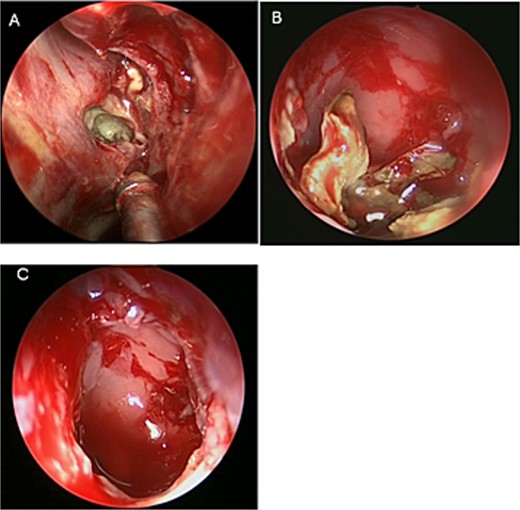

A 69-years-old diabetic female was referred from neurology as she complained of an acute onset severe headache, diplopia, and retro-orbital pressure. An initial CT scan with a subsequent MRI scan (Fig. 5) showed infiltrative sphenoid pathology invading both skull base and cavernous sinus given a provisional diagnosis of acute invasive fungal sinusitis. The patient was urgently taken to the operative theater to endoscopically debride sphenoid sinuses (Fig. 6). Histopathological examination confirmed the diagnosis of invasive sphenoid sinus mucormycosis.

Intra-operative endoscopic view of shenoid sinus debridement of invasive fungal disease.